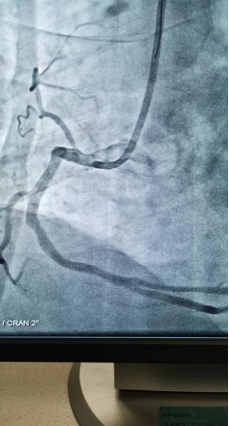

日前,商城县人民医院胸痛中心群里在半个小时内先后报告了两例来自李集乡的急性心梗患者,一场与时间赛跑,与死神博弈的生死急救快速拉开了帷幕!

急诊PCI对医院的硬件、人员配备等要求极高,能否开展急诊PCI目前已成为心血管领域彰显医院整体诊疗水平的标志。一台台成功的手术、一个个因救治及时而重获新生的患者,无不体现着我院胸痛中心日臻成熟的精确诊疗技术!也显示出我院在介入治疗领域已具备较强的综合实力。不论白昼还是黑夜、疾风或是暴雨,胸痛中心的电话就是命令!时间就是生命,时间就是心肌,胸痛中心团队始终秉持着生命至上、人民至上的理念,他们每天与时间赛跑,与死神搏斗!节省的每一分每一秒都在为急性心肌梗死患者争取生的希望,力求实现胸痛救治从急救到预防,从急病到慢病的延伸,随时待命为大别山区广大心血管疾病患者保“心”护航!